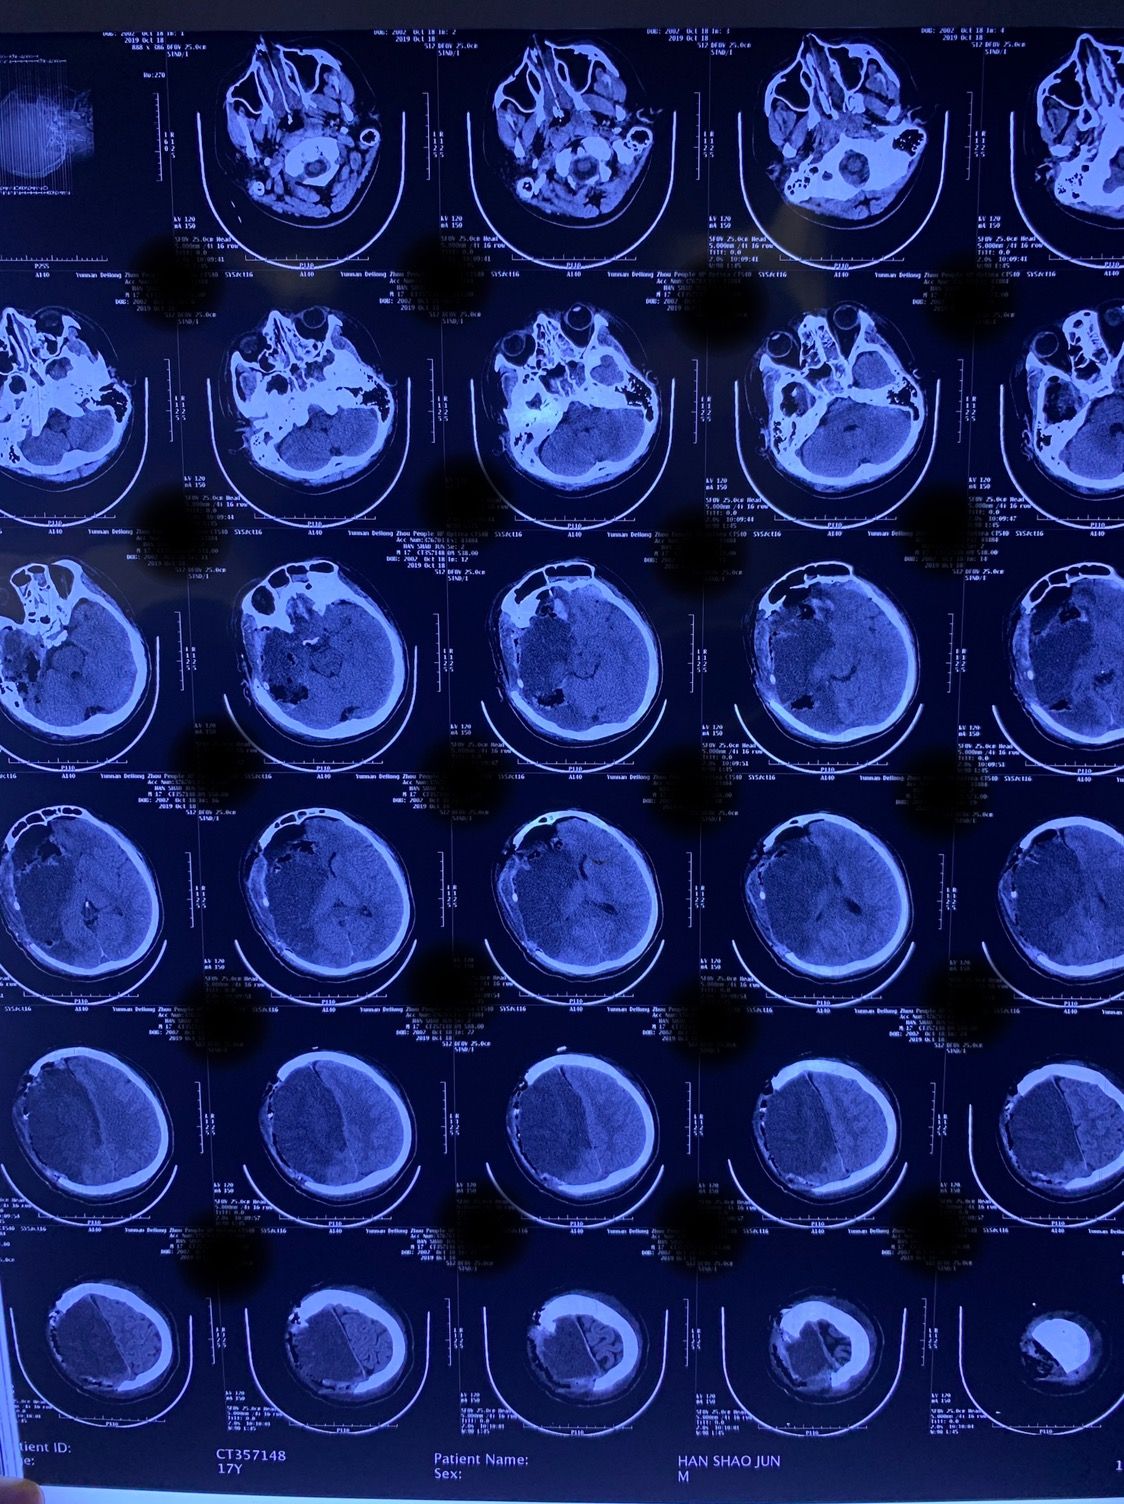

因病情危重,家属决定转院。于伤后11小时送至德宏州医院进一步治疗。患者于10月16日23时左右突发右侧瞳孔散大,急诊复查头颅CT示右侧额颞顶枕大面积脑梗死。

遂急诊行右侧额顶颞枕去骨瓣减压术,术后脑肿胀仍明显,骨窗张力极高。于10月17日请昆明医科大学第二附属医院神经外科蒲军主任会诊,蒲军主任详细了解病情并仔细分析影像学资料后决定再次手术扩大去骨瓣范围,并同时行内减压术。

再次手术后于10月18日复查CT